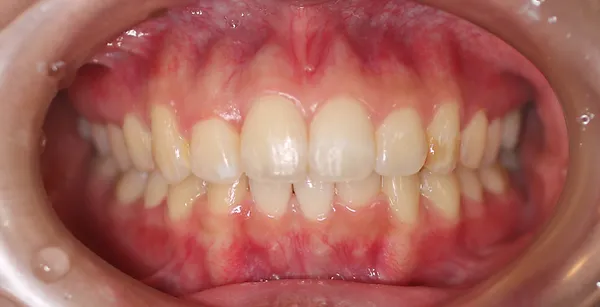

2ホワイトニング【治療例1】

治療前

治療後